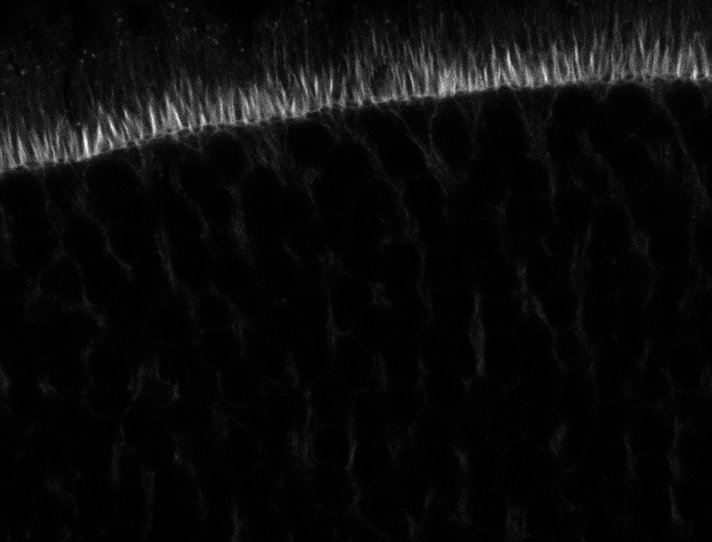

Actin